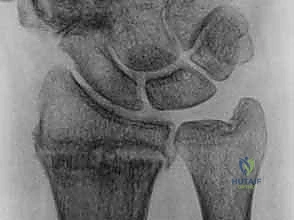

التشريح الدقيق والميكانيكا الحيوية لعظم الزند

لفهم مدى تعقيد كسور عظم الزند وكيفية علاجها، يجب علينا أولًا فهم التشريح الهندسي الرائع لهذه المنطقة الحيوية من الساعد. يتكون الساعد البشري من عظمتين متوازيتين: الكعبرة والزند. يعملان معًا كوحدة وظيفية متكاملة.

دور الزند كنقطة ارتكاز محورية (The Fulcrum)

- نقطة الارتكاز الثابتة: على عكس الكعبرة التي تتحرك وتدور، يُشكل الطرف البعيد للزند (عند المعصم) نقطة ارتكاز شبه ثابتة. تدور اليد والكعبرة حول رأس الزند في حركة تشبه حركة الباب حول مفصلاته. هذه الوظيفة المحورية تضمن أداء معظم الأنشطة اليومية لليد بسلاسة وثبات.

- المفصل الزندي الكعبري البعيد (DRUJ): هو المفصل الذي يربط بين نهايات الكعبرة والزند عند المعصم. يدور عظم الكعبرة حول رأس الزند من خلال هذا المفصل أثناء حركات الكب (تدوير الساعد بحيث يكون باطن اليد لأسفل) والبسط (تدوير الساعد بحيث يكون باطن اليد لأعلى). استقرار هذا المفصل لا يعتمد فقط على العظام، بل يعتمد بشكل كبير على التوافق العظمي بين رأس الزند والثلمة الكعبرية (الشق السيني - Sigmoid Notch) في الكعبرة.

المركب الغضروفي الليفي الثلاثي (TFCC) وأهميته القصوى

يُعد المركب الغضروفي الليفي الثلاثي (Triangular Fibrocartilage Complex - TFCC) بمثابة "غضروف الركبة" بالنسبة للمعصم. إنه هيكل معقد يتكون من أربطة وغضاريف تربط المفصل الزندي الكعبري البعيد بعظام الرسغ.

* وظيفة الـ TFCC: يوفر استقرارًا حيويًا للمفصل (DRUJ)، ويساعد في امتصاص الصدمات وتوزيع الأحمال الميكانيكية عبر المعصم أثناء رفع الأشياء الثقيلة أو الاستناد على اليد.

* الارتباط بالناتئ الإبري: ترتبط العديد من أربطة الـ TFCC مباشرة بالناتئ الإبري للزند (Ulnar Styloid). لذلك، فإن أي كسر في قاعدة الناتئ الإبري غالبًا ما يصاحبه تمزق في هذا المركب الغضروفي، مما يؤدي إلى عدم استقرار شديد في المعصم يستوجب تدخلًا جراحيًا دقيقًا، وهو ما يبرع فيه الأستاذ الدكتور محمد هطيف باستخدام تقنيات المناظير (Arthroscopy).

الأربطة الزندية الكعبرية (Radioulnar Ligaments)

تُعتبر الأربطة الزندية الكعبرية (الظهرية والراحية) حاسمة لاستقرار المفصل. تنشأ هذه الأربطة من نقرة رأس الزند (Fovea) وقاعدة الناتئ الإبري، وتتصل بالحواف الظهرية والراحية للثلمة الكعبرية.

في الوضع المحايد للساعد، تكون حوالي 60% من الأسطح المفصلية في تماس مباشر. ولكن، المثير للاهتمام طبيًا هو أن هذا التماس ينخفض إلى 10% فقط في حركات الكب والبسط الكاملة. هذا يعني أنه في أقصى درجات دوران اليد، تصبح العظام غير قادرة على تثبيت المفصل بمفردها، وهنا يبرز الدور الحيوي والجوهري للأربطة في الحفاظ على المفصل من الخلع (Dislocation).